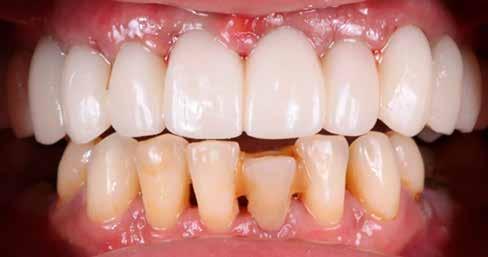

1. a–d. ábrák: Kiindulási klinikai állapot a két páciens esetében: Az első páciensnél a jobb felső premolárisok és az első moláris, a második páciensnél a bal felső második premoláris.

heléssel vagy anélkül). Az első páciensnél gyökérreszorpció miatt szükségessé vált a jobb felső premolárisok és az első moláris eltávolítása (1. a–b ábrák). A második páciensnél a bal felső második premoláris frakturát szenvedett (1. c–d ábrák) Az átfogó tervezést és diagnosztikát CBCT-felvétel segítségével végeztük (2. a–c ábrák), a posztoperatív kontroll és az utánkövetés időszakában pedig periapikális röntgenfelvételeket készítettünk. A jelen tanulmányban résztvevő valamennyi páciens nemdohányzó volt, jó, vagy gyógyszeresen jól karbantartott általános egészségi állapotnak örvendett. A hatékony plakk-kontroll ellenére műtét előtt mindkét páciensnél végeztünk supragingivális depurálást és gyökérsimítást.